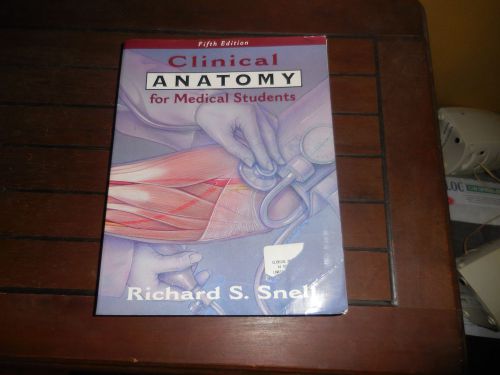

Clinical Anatomy for Medical students (Fifth Edition) by Richard S. Snell